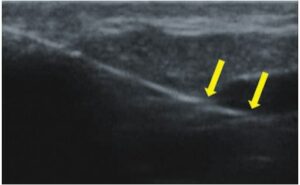

Die Doppler-Sonographie ermöglicht die Darstellung großer Gefäße und Perforatoren, die sich meist in tieferen Bereichen des subkutanen Gewebes befinden. Mit klassischem Ultraschall lassen sich kleinere Gefäße jedoch nicht darstellen. Für die Darstellung kleinerer Gefäße, die oberflächlich unter der Epidermis und im oberen subkutanen Gewebe liegen, wird HFU eingesetzt. Mit Sonden über 20 MHz Frequenz erhält man hochauflösende Ultraschallbilder, auf denen Objekte kleiner als 0,1 mm unterscheidbar sind. Mit zunehmender Auflösung nimmt jedoch die Eindringtiefe ab. Je nach Sonde und Gerät beträgt die maximale Eindringtiefe etwa 20–30 mm. Diese Eindringtiefe bei gleichzeitig hoher Bildauflösung ermöglicht die Beurteilung sehr kleiner Gefäße. HFU erlaubt die genaue Bestimmung des Verlaufs und der Lage kleiner Gefäße in der Haut, was entscheidend für die Wahl der Verschlussmethode und die Planung des Eingriffs ist. Oft sind an der Hautoberfläche nur wenige Gefäße sichtbar – erst durch die Ultraschalluntersuchung lässt sich die tatsächliche Anzahl und der Verlauf feststellen. Für einen erfolgreichen Verschluss muss das gesamte Gefäß behandelt werden, nicht nur der sichtbare Teil, da sonst eine schnelle Rekanalisation erfolgt (7). Häufig ändert das an der Haut sichtbare Gefäß seinen Verlauf, wird gewundener und zieht in tiefere Hautschichten (8). HFU ermöglicht zudem die Darstellung der Perforatoren zwischen kleinen Gefäßen und die Messung grundlegender Parameter wie Durchmesser, Wandstärke, Tiefe und Blutfluss (6). Mit der 40-MHz-Sonde von Ultrasonix kann auch der Blutfluss mittels Farbdoppler visualisiert werden.

Transkutane Laserbehandlungen zum Verschluss von Gefäßen gewinnen an Popularität. Dabei wird Lichtenergie von Hämoglobin in den Erythrozyten absorbiert und in Wärme umgewandelt, was die Gefäßwand koaguliert. Bei kleinen Teleangiektasien ist der Effekt sofort sichtbar, bei retikulären Venen erfolgt der Verschluss erst Wochen nach dem Eingriff (9). Der Erfolg hängt von den gewählten Parametern ab. Die genaue Bestimmung der Gefäßtiefe und des Durchmessers ist entscheidend. HFU ermöglicht präzise Messungen, auf deren Grundlage Laserart, Wellenlänge, Impulsdauer, Spotgröße und Energiedichte festgelegt werden (7). HFU dient auch der Überwachung der Korrektheit und Wirksamkeit des Eingriffs.

Sklerotherapie verschließt Gefäße durch Injektion eines chemischen Obliterans. Sie ist kostengünstig und relativ einfach durchzuführen. Hauptsächlich für retikuläre Venen >3 mm, kann aber auch bei kleineren Gefäßen eingesetzt werden (10). Bei Gefäßen <3 mm ist die Punktion schwierig, wodurch Komplikationen wahrscheinlicher werden (7). HFU hilft hier, den Gefäßverlauf exakt darzustellen und den Eingriff unter Ultraschallkontrolle durchzuführen, wodurch das Risiko einer Nekrose durch Fehlinjektion minimiert wird. HFU überwacht zudem die Wirksamkeit des Eingriffs.